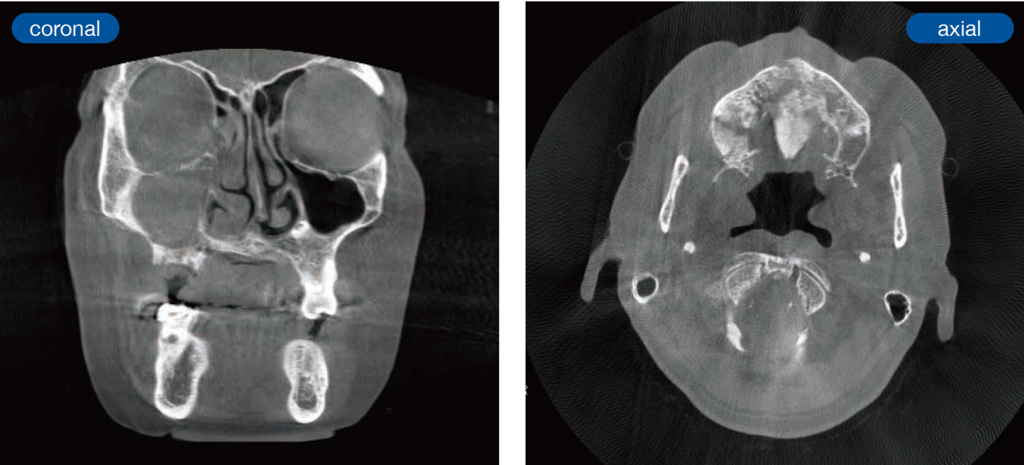

初診時:単純CT画像

右側上顎洞内には陰影を認め、上顎右側前歯部から臼歯部にかけての腐骨様組織を認めた。

初診4か月前と初診時:骨SPECT/CT画像の比較

原因となった右上6部から近心に向かって、右上2にかけて骨の腐骨化が進行してきている。

顎骨の粗造部分に一致してRI薬剤の集積が抜けており、周囲の骨に集積している像が見られた。